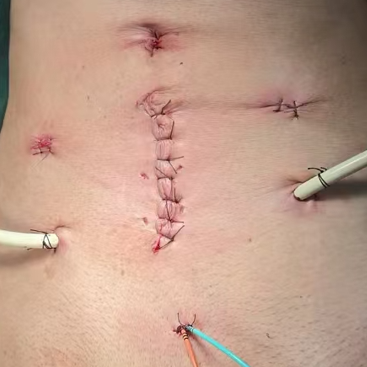

多年来,贵州航天医院各科室紧跟医学前沿,不断强技术、补短板,大力开展新技术、新项目,完成了许多高精尖、高难度、本地区“首例”的技术,填补了医院医疗技术空白,满足了群众日益增长的医疗需求。 本期,我们将为大家带来泌尿外科特色技术——腹腔镜膀胱癌根治术+原位新膀胱术,保留患者自然排尿功能。 案例分享 患者(60岁)在当地医院检查发现膀胱多发肿瘤,在行膀胱肿瘤电切术后,病理提示:高级别尿路上皮癌,该院医生建议患者进行根治性膀胱切除,但切除后肚子上将存在永久造瘘并需佩戴腹壁尿袋,尿液不能自己控制,随时会从肚子流出。 患者拒绝接受挂尿袋的方式,在辗转多个医院咨询后,得知贵州航天医院泌尿外科具有切除膀胱后肚子上不用佩戴尿袋的技术,于是前来我院就诊。泌尿外科腔镜组组长李凯教授带领团队经过反复研究病史及阅片,充分考虑患者需求并征得患者及家属同意后,决定为患者实施腹腔镜根治性膀胱切除术+原位回肠新膀胱术。 CT示膀胱内多发肿瘤 经过6个多小时紧张的手术,顺利切除膀胱并取长约40cm的肠管重新整合成新膀胱,再与输尿管、尿道吻合后原位代替病变的膀胱。切除的组织经过病理检测,提示:恶性上皮肿瘤,符合膀胱高级别浸润性尿路上皮癌,侵及深肌层。 术后3天,患者可以正常排尿;1周后顺利出院;1月后拔出双侧单J管及尿管,患者反馈小便顺畅,无尿失禁等不良情况出现;3月后患者进行尿流率检测,自主排尿通畅。 术后腹壁伤口愈合良好 患者术后3月新膀胱影像 术后3月,患者行尿流率检测 自主排尿通畅 腹腔镜膀胱癌根治术+原位新膀胱术代表了现代泌尿外科技术的最高水平,它不仅为膀胱癌患者提供了根治肿瘤的机会,还通过微创技术和功能重建,帮助患者重获高质量的生活。贵州航天医院泌尿外科李凯教授团队结合患者实际情况对该技术进行了改良,全手工缝合新膀胱,确保患者排尿正常且避免了结石等并发症的出现,已完成多例手术,在遵义地区处于一流水平,为遵义地区患者健康保驾护航。 咨询信息:贵州航天医院便民服务电话 什么是腹腔镜膀胱癌根治术+ 原位新膀胱术 膀胱癌是泌尿系统常见的恶性肿瘤之一,传统的手术方式虽然有效,但创伤大、恢复慢,患者需终生佩戴腹壁尿袋,生活不便且影响社交,给患者带来了极大的身体和心理负担。随着医学技术的不断进步,腹腔镜膀胱癌根治术+原位新膀胱术成为治疗膀胱癌的先进选择,以其精准、微创、恢复快的优势,为患者带来了新的选择和希望。 腹腔镜膀胱癌根治术+原位 新膀胱术原理 腹腔镜膀胱癌根治术是一种微创手术,通过腹腔镜技术,医生可以在高清影像的引导下,精准切除病变的膀胱及周围可能受侵的组织。与传统开腹手术相比,腹腔镜手术切口小、出血少、术后疼痛轻,患者恢复更快。 原位新膀胱术则是在切除膀胱后,利用患者自身的肠道组织(通常为回肠)构建一个新的膀胱,并将其与尿道连接,使患者能够通过正常途径排尿,极大提高了术后生活质量。相比传统的尿流改道术(如回肠代膀胱术),原位新膀胱术更符合生理结构,患者无需佩戴尿袋,生活质量显著提升。 腹腔镜膀胱癌根治术+原位 新膀胱术优势 (一)微创精准,减少创伤 腹腔镜手术通过几个小切口完成操作,避免了传统开腹手术的大切口,减少了术中出血和组织损伤,术后疼痛轻,恢复快。 (二)原位新膀胱,恢复自然排尿功能 原位新膀胱术重建了患者的排尿功能,术后患者可以通过尿道正常排尿,避免了佩戴尿袋的不便和心理压力。 (三)术后并发症少,恢复快 由于手术创伤小,术后感染、肠梗阻等并发症的发生率显著降低,患者住院时间短,能够更快回归正常生活。 (四)提高生活质量 原位新膀胱术不仅保留了患者的排尿功能,还减少了术后对生活的影响,患者可以更好地融入社会和工作。 术后康复与护理 术后患者需遵循医生的指导,逐步恢复饮食和活动。早期可能需要进行膀胱功能训练,以适应新膀胱的排尿功能,定期复查和随访是确保术后长期效果的关键。 友情提醒: 发现无痛性肉眼血尿,需警惕泌尿系肿瘤,尤其是发病率较高的膀胱癌,须尽早就诊。 贵州航天医院泌尿外科专家团队 石 英 泌尿外科主 任 学科带头人 主任医师 中国医师协会泌尿外科分会感染协作组委员,奥林巴斯泌尿系软镜西南区专家组成员,西南地区第一批输尿管软镜专家组成员,贵州省医学会泌尿外科分会委员,贵州省性学会理事,贵州省性学会常务委员,贵州省泌尿外科专业医疗质量控制中心专家委员会委员。 从事泌尿外科专业近30年,熟练掌握泌尿系各类疾病的诊治,具有丰富的临床经验,擅长泌尿系结石、腹膜后肿瘤及泌尿系肿瘤的手术治疗,对泌尿系感染、泌尿系结核、尿源性脓毒血症的救治有独到的见解及抢救经验,在贵州省率先引入输尿管软镜技术,同时在男科领域,对男性阳痿、早泄及前列腺疾病有很深的研究。 李 凯 泌 尿 外 科 副 主 任 医 师 贵州航天医院肿瘤腔镜组带头人,擅长肾癌根治术、输尿管癌根治术、膀胱及前列腺癌根治术、腹腔镜输尿管狭窄切除吻合术、输尿管切开取石术等手术,在遵义市率先开展泌尿系结核后膀胱挛缩全腹腔镜下膀胱扩大术。 贵州省医学会泌尿外科分会青年委员,遵义市医学会男科分会常务委员,遵义市医学会泌尿外科分会常务委员。 李国成 泌 尿 外 科 副 主 任 医 师 中国人体健康科技促进会男科学专业委员会委员,贵州省性学会泌尿外科分会委员,贵州省医学会男科学分会委员,遵义市医学会男科学分会副主任委员兼秘书长,遵义市医学会泌尿外科分会常务委员,贵州航天医院男科带头人。 从事泌尿外科及男科工作10余年,曾多次在上海交通大学附属第一人民医院,中国中医科学院西苑医院进修学习男科;擅长性功能障碍的诊治,男性整形手术,前列腺增生激光手术,显微手术等。 贵州航天医院泌尿外科简介 • ✦ 基本情况 ✦ • 贵州航天医院泌尿外科创建于1968年,经过几代人的努力,微创与内镜手术占比达90%以上。是贵州省临床重点专科建设单位、北京清华长庚医院李建新教授团队诊疗及会诊中心、北京医学会尿路修复与重建诊疗及会诊中心、上海公济泌尿外科集团遵义中心、上海援黔专家李铮教授男科工作室、贵州省泌尿外科质量控制专家委员单位,科室亚专业框架已完善。 • ✦ 专科特色技术 ✦ • (一)泌尿系结石内镜碎石技术 泌尿系结石微创治疗领域方面是贵州省首家引进科医人钬激光碎石技术科室,在遵义地区率先掌握输尿管硬镜、软性镜,经皮肾镜钬激光碎石技术。目前是北京清华长庚医院泌尿外科“手把手”经皮肾镜碎石技术培训基地、贵州省输尿管软镜培训基地。 1.负压吸引可弯曲软镜鞘电子软镜碎石术 2.标准与超微通道相结合的经皮肾镜碎石取石术 (二)微创腹腔镜技术 泌尿外科腹腔镜技术师承于浙江省人民医院、北大、北京解放军总医院。目前采用经腹、经后腹双入路法的腹腔镜技术完成肾部分切除、肾切除、肾输尿管全长切除、肾盂输尿管成形、输尿管狭窄吻合、膀胱翻瓣等手术。在遵义地区率先掌握腹腔镜下膀胱癌根治术、腹腔镜下前列腺癌根治术。 (三)男科、盆底技术临床应用 遵义地区男科分会主委单位,是贵州省首家引进尿动力学检查并取得了全国资质认证科室,也是贵州省首家进行RigiScan检查的单位。在遵义地区率先掌握显微取精子技术以及显微镜下治疗精索静脉曲张、显微镜下输精管吻合、输精管附睾吻合技术。率先采用前列腺激光剜除术治疗前列腺增生症。在陆军军医大学西南医院泌尿外科主任沈文浩教授指导下,完成遵义市首例神经源性膀胱骶神经调节刺激器置入术。 • ✦ 诊疗范围 ✦ • 诊疗范围(除外肾移植、癌栓):泌尿系结石、泌尿系肿瘤、肾上腺疾病、肾积水、前列腺增生、男性生殖器功能障碍(精索静脉曲张、生殖道感染、输精管梗阻等)、盆底功能障碍性疾病(膀胱脱垂、排尿功能异常、尿失禁)、泌尿生殖系畸形。 泌尿外科拥有独立门诊治疗室、日间手术室、尿动力学检查室、精液分析检查室、男性勃起功能检查及治疗室、ESWL治疗室、结石分析检查室。